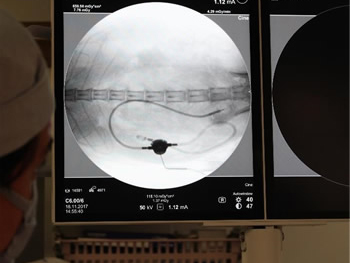

造影で漏れがないか何度も確認

必ず透視下にて漏れがないか何度も確認をします。 透視をしないとシステムや装着部分からの漏れが確認されたり、トラブルが考えられます。

実際、他院で装着して漏れがあるなどの相談をうけることがしばしばあります。

透視下にて実施すれば適切な位置に装着できます。

透視下にて腎盂に入っていることを確認。

ここにカテーテルを装着していきます。